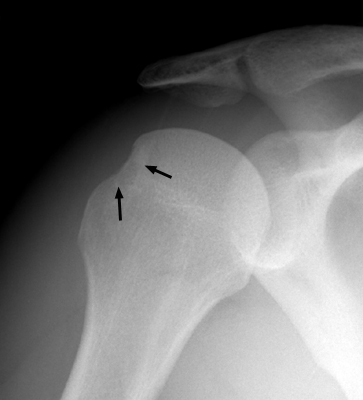

Return to Hill-Sachs Fracture